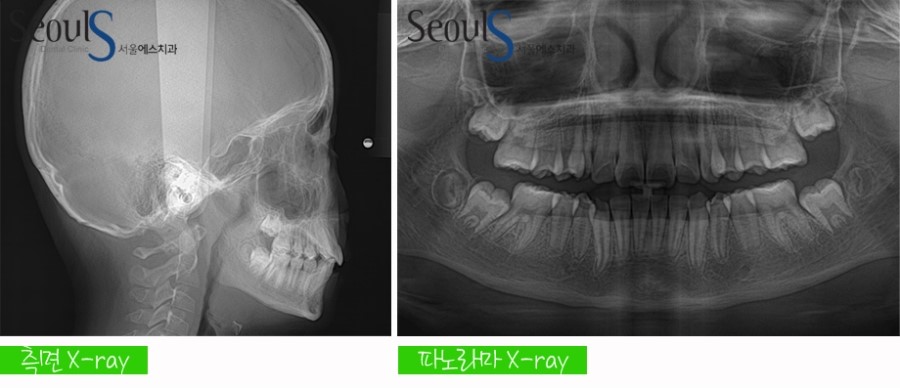

진단 과정입니다

파노라마 X-ray 촬영 , 측면 X-ray 촬영, 진단 모형 제작 및 3차원 분석 후  컴퓨터 교정 진단프로그램에 입력해

진단하며 환자분께 가장 좋은 교정 방법을 제시해드립니다